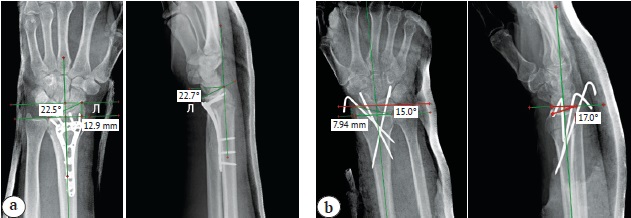

Нами были изучены и проанализированы основные рентгенологические параметры поврежденного сегмента лучевой кости как на предоперационном этапе, так и после операции (рис. 1, 2, 3).

Рис. 3. Измерение и оценка основных рентгеноанатомических параметров лучезапястного сустава после выполнения малоинвазивного остеосинтеза: a — после остеосинтеза пластиной; b — после перкутанного остеосинтеза спицами

Fig. 3. Measurement and assessment of the main radiographical parameters after minimally invasive osteosynthesis: a — after volar locking plate fixation; b — after percutaneous K-wiring

Представленные группы были сопоставимы по всем дооперационным рентгенологическим параметрам: сопоставимость групп по типу перелома установлена с помощью критерия χ2 Пирсона (р = 0,281), по ладонному наклону суставной фасетки лучевой кости (р = 0,259), по высоте лучевой кости (р = 0,916) и по инклинации лучевой кости (р = 0,203) с помощью U-критерия Манна – Уитни.

Сравнительные результаты оценки восстановления основных рентгеноанатомических параметров ДМЛК в обеих группах в динамике представлены в таблице 1.